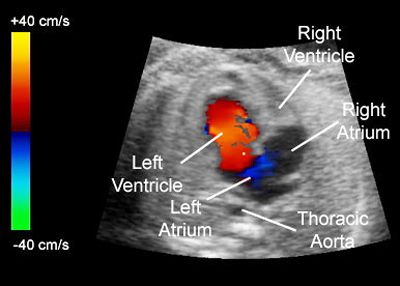

Color Doppler

The color Doppler ultrasound is a technique that allows evaluates blood vessels. In this technique the physician to recognize the direction and speed of blood flow inside a vessel or heart chamber. It has a doctor also check for injuries to your arteries or to monitor certain treatments to your veins and arteries. The Parijat hospital provides Color Doppler in hospital lab. Generally it takes 15-20 minutes.